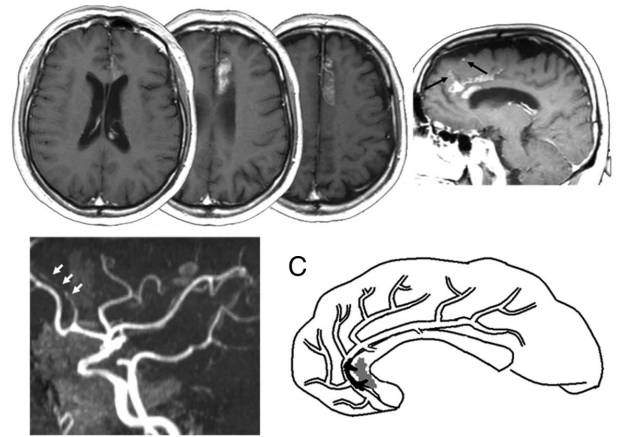

图4 增强磁共振扫描提示胼胝体和扣带回的梗死,矢状位图像提示额上回也有受累。MRA提示大脑前动脉A2和A3段闭塞。C为模式图,黑色部分为血栓,灰色部分为梗死区。

动脉到动脉栓塞

图5 DWI提示皮层多发梗死灶。MRA可以发现左侧A2-A3交界处明显狭窄。